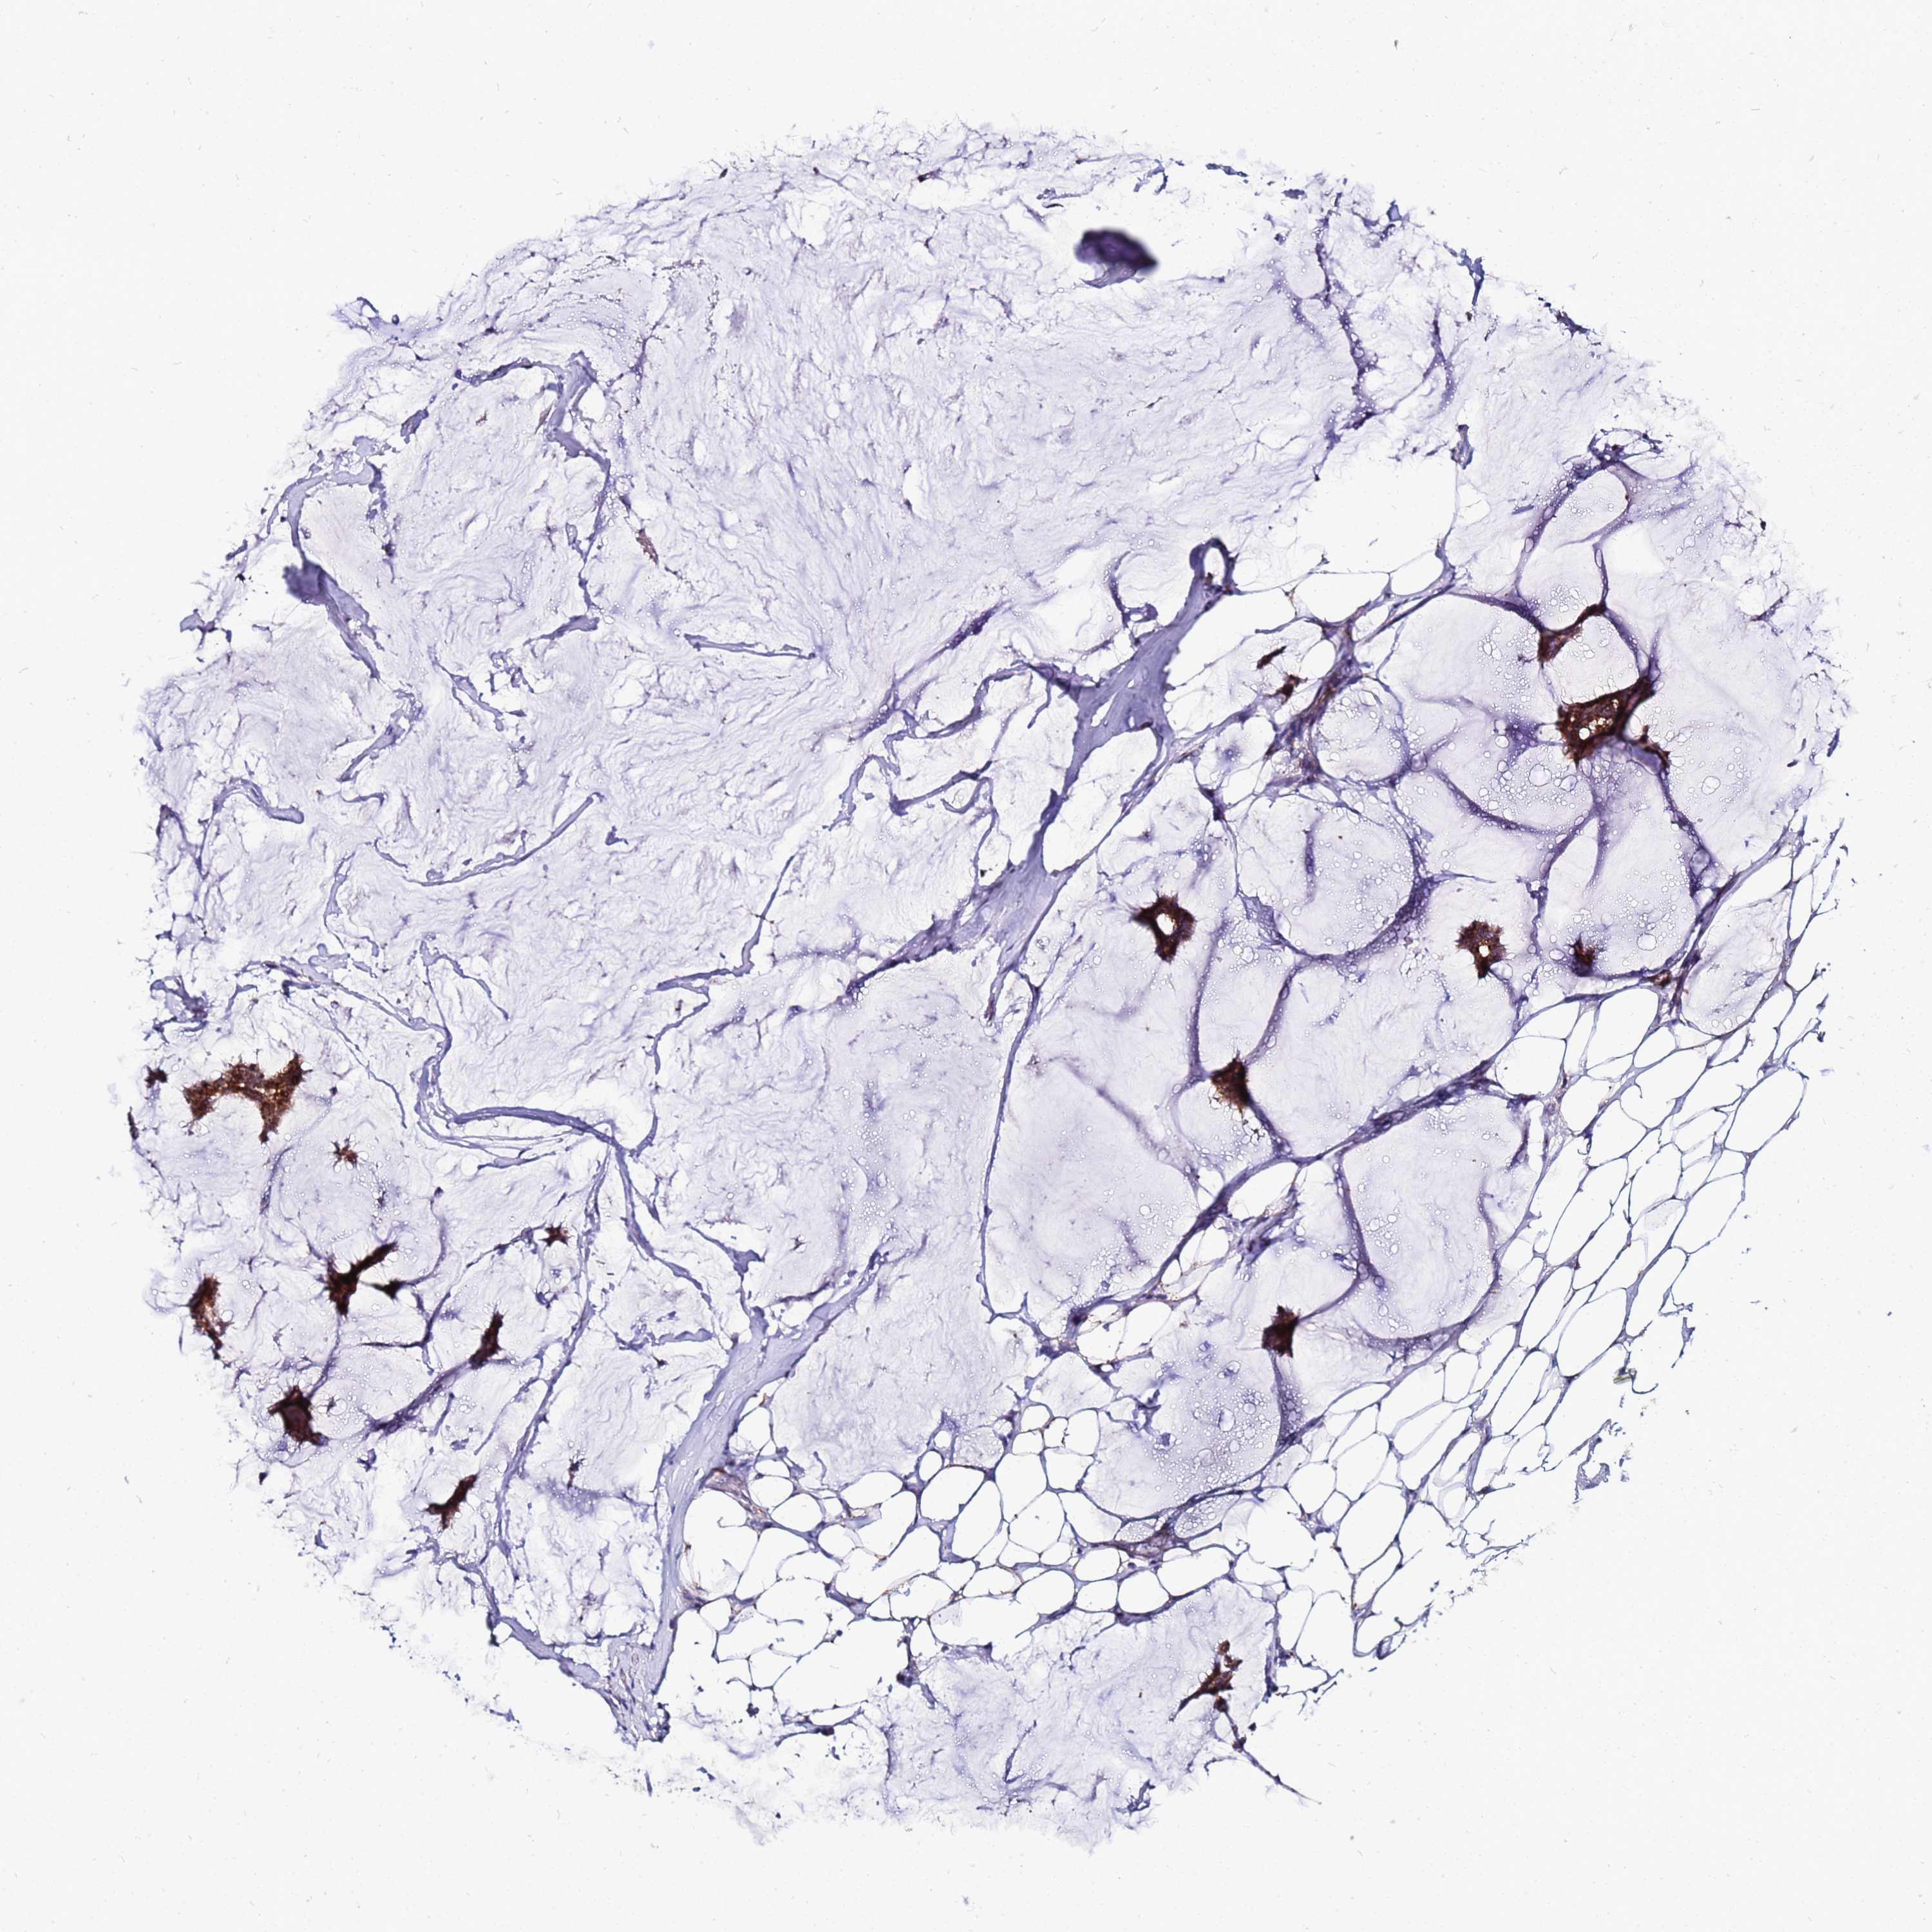

CANCER BREAST CANCER Show tissue menu

BRCA TCGA BRCA VALIDATION PROTEIN EXPRESSION